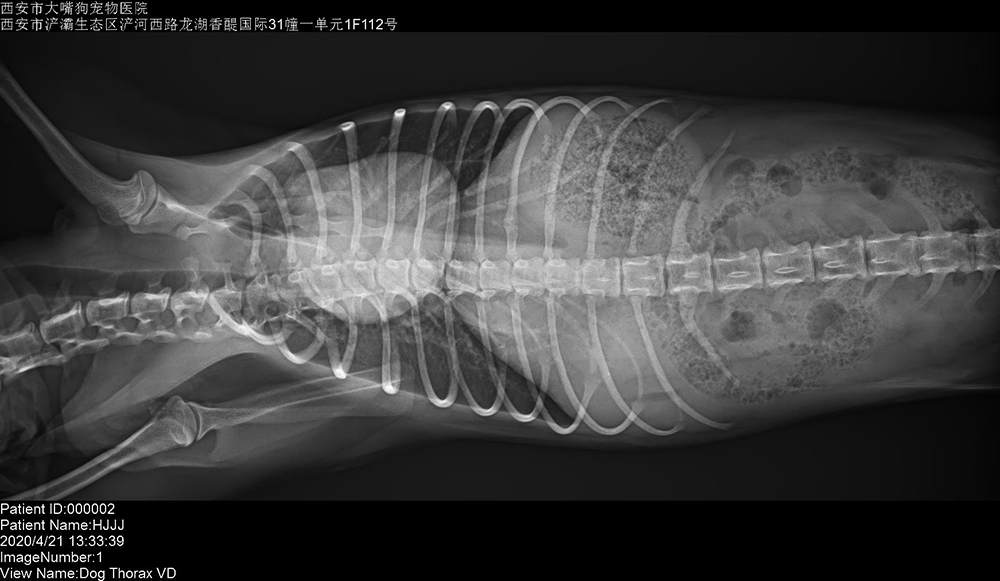

陝西(xī)西(xī)安大(dà)嘴狗寵物(wù)醫(yī)院 2020/4/26 上(shàng)一(yī)篇: 新疆北(běi)屯雅馨寵物(wù)服務中心 下(xià)一(yī)篇: 山(shān)東(dōng)青島欣康寵物(wù)醫(yī)院